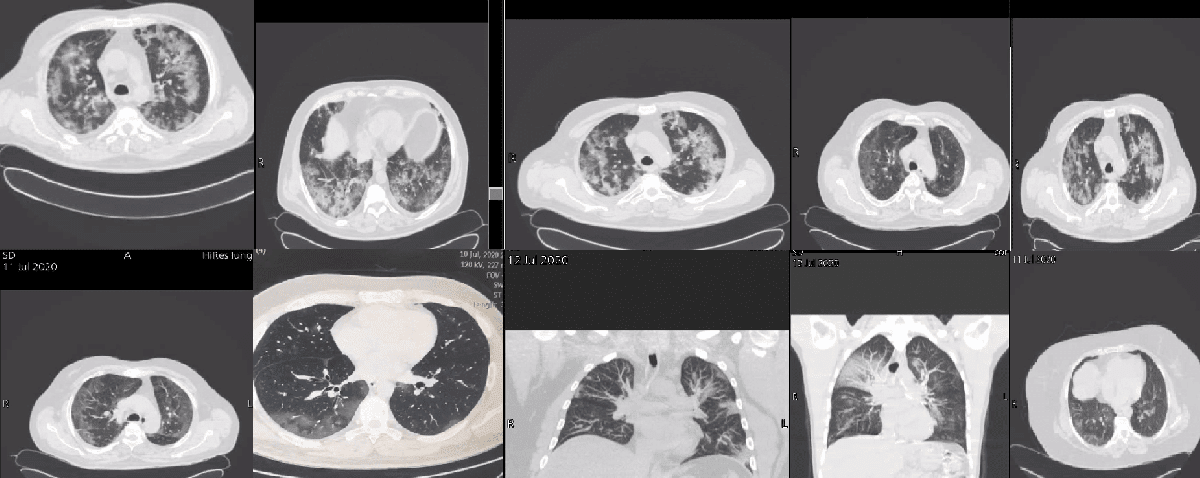

واضاف الطبيب الجندي" كل مرة تسعل فيها ستشعر بألم حاد في صدرك و ذراعيك و عينيك ، إذا توقف الأمر عند هذه المرحلة فأنت من المحظوظين، و لكن إذا تمكن منك هذا المرض فستحاول جاهدا إدخال الهواء لرئتيك و لكنك لا تستطيع، ستحاول التنفس بسرعة أكثر فأكثر و لكن ستبدأ لاحقا في الشعور بالفشل في عضلات تنفسك التي ستنهار".

وتابع : ستشعر بالقلق و الخوف من الموت القريب منك ، حينها سأتدخل أنا وزملائي و نحاول وضع قناع تنفس على أنفك لتزويدك بالأكسجين الذي لم تعد رئتك قادرة على الحصول عليه وإذا لم يساعدك ذلك وبدأت حالتك في التأزم سأقوم بإدخال أنبوب عبر حلقك، ستشعر بألم شديد و اختناق عند إدخاله، لن أتوقف عند ذلك بالطبع سأواصل إدخاله حتى يصل لنهاية قصبتك الهوائية ولن تستطيع الكلام أو الأكل أو الشرب ".